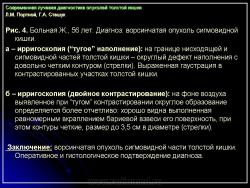

3. Симптом округлой (овальной) формы дефекта наполнения в просвете кишки:

– со всех сторон покрытый мелкими вкраплениями бариевой взвеси, что характеризует, как правило, ворсинчатую опухоль кишки (рис. 4);

Л.М. Портной, Г.А. Сташук